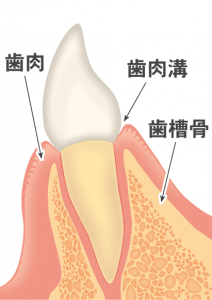

歯周病とは

歯周病菌や噛む力の影響で、歯茎が腫れたり、歯を支えている骨(歯槽骨)が溶けてしまう病気です。